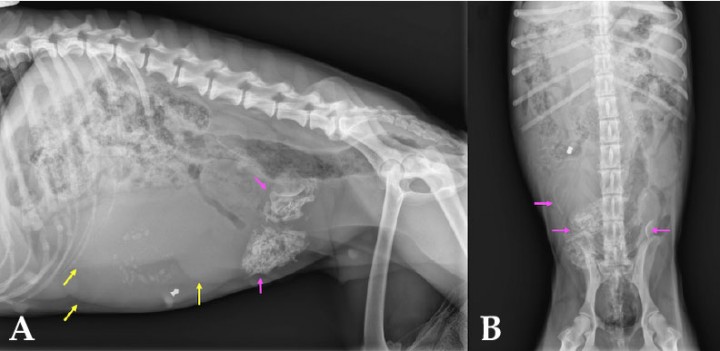

<p>Radiografías del abdomen. (<strong>A</strong>) Proyección laterolateral derecha. (<strong>B</strong>) Proyección ventrodorsal.</p>

Radiografías del abdomen. (A) Proyección laterolateral derecha. (B) Proyección ventrodorsal.

En ambas proyecciones se visualiza buena definición de serosas y se aprecian varias masas de morfología tubular y opacidad tejido blando que ocupan gran parte del abdomen medio y caudal, produciendo un efecto masa con desplazamiento dorsocraneal de estómago, asas intestinales y colon. A nivel del abdomen medio ventral y caudal se observan unas estructuras de opacidad hueso, así como otra de opacidad metal cuya morfología es compatible con la de un balín localizado en abdomen medio ventral, en el lado derecho (Fig. 2).

Mismas radiografías de la Figura 1. Se observan masas de morfología tubular y opacidad tejido blando que generan efecto masa (flechas amarillas), así como estructuras de opacidad hueso (flechas rosas) en su interior.